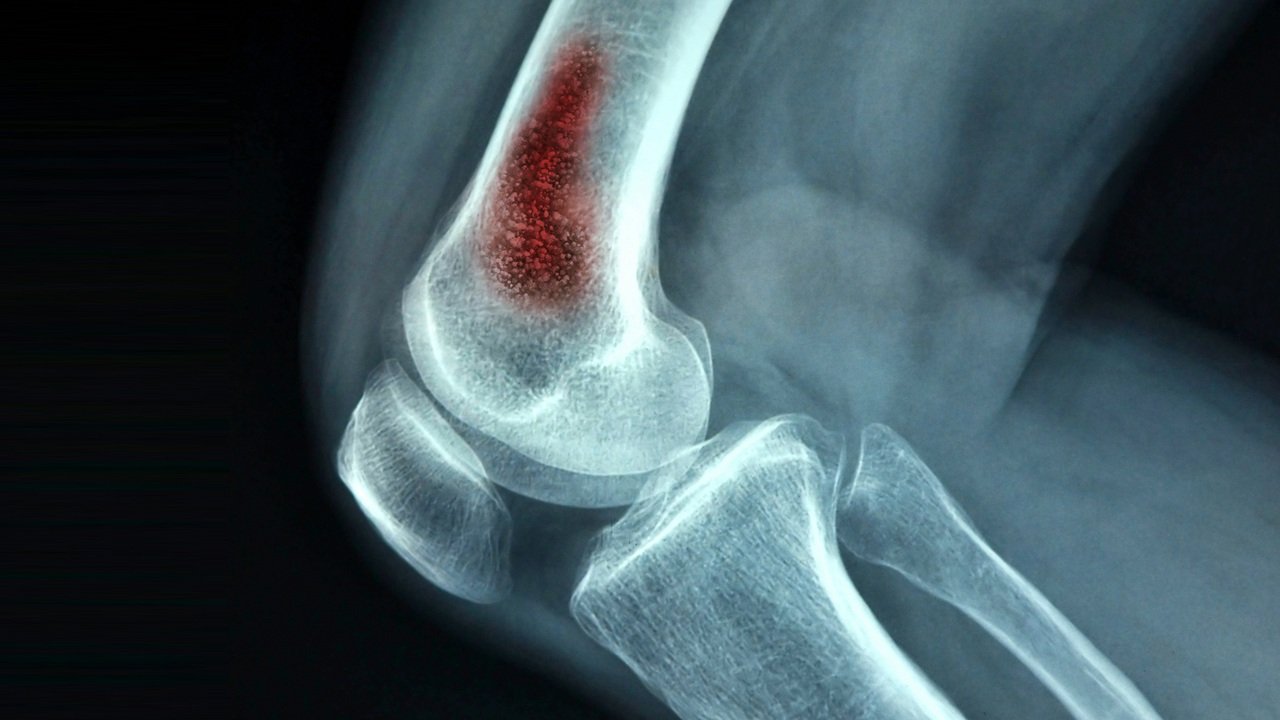

التهاب العظام الصديدي (تسوس العظام) والذي يُعرَف كذلك باسم التهاب العظم والنقى، والنقى هو السائل الموجود داخل العظام، مرض يهدد سلامة العظام إذا ما تم إهمال علاجه.

وهو عبارة عن عدوى تصيب العظام ويحدث نتيجة وجود بكتريا (ميكروب) فى العظام. وقد تصل البكتريا إلى العظام من أنسجة أخرى في الجسم مسببةً التهاب العظام الشديد. عادة ما تتسبب بالبكتيريا في العدوى، ولكن يمكن، في حالات قليلة، أن تسببها الفطريات أو الفيروسات.

يصيب التهاب العظم والنقي 2 من كل 10000 شخص، من الأطفال والبالغين، وقد يسبب ألمًا وتورمًا في المناطق المصابة، وحمى، وتصريفًا للقيح، بالإضافة إلى أعراض أخرى.

علاج التهاب العظام الصديدي يبدأ بمعرفة نوع العدوى البكتيرية وتناول المضادات الحيوية المناسبة، ثم الجراحة إذا استدعى الأمر. ولتجنب الجراحة، يجب العرض على الطبيب فور ظهور أعراض التهاب العظم. إذا لم يتم علاج الإلتهاب الصديدي بصورة سليمة، يتحول إلى إلتهاب مزمن ويتسبب في فقدان إمدادات الدم، مما قد يؤدي في النهاية إلى موت أنسجة العظام (تنخر العظام) وتلفها.